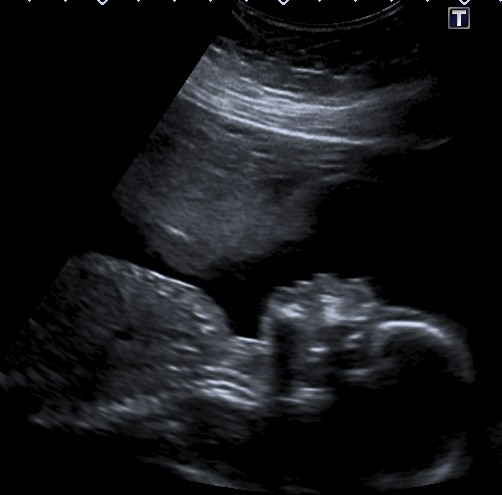

Кровотечения повторялись регулярно, и каждый раз Стейси думала, что это конец, пока на 20-й неделе на новом обследовании не обнаружилось нечто странное. На скане УЗИ над младенцем появился силуэт, напоминающий профиль человека. Стейси решила, что это ангел-хранитель, который следит за её сыном. Трудно сказать, правда это или нет, но женщине удалось родить без осложнений, хоть малыша и пришлось сразу отправить на лечение из-за сепсиса. Сейчас ему четыре года, и никаких проблем со здоровьем у него нет.